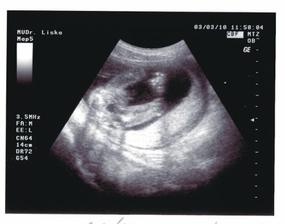

02.03.2010 (20.tt) - Genetický ultrazvuk:máme podrobně prozkoumané miminko, vše je v pořádku, pouze zjištěna mírná dilatace ledvinných pánviček cca 5 mm, dostali jsme doporučení na kontrolní ultrazvuk za měsíc.

03.03.2010 (20.tt) - Na vlastní žádost další ultrazvuk u jiného Dr., abychom dostali mimi na videu - máme úžasný zážitek a ještě úžasnější památku na celý život!